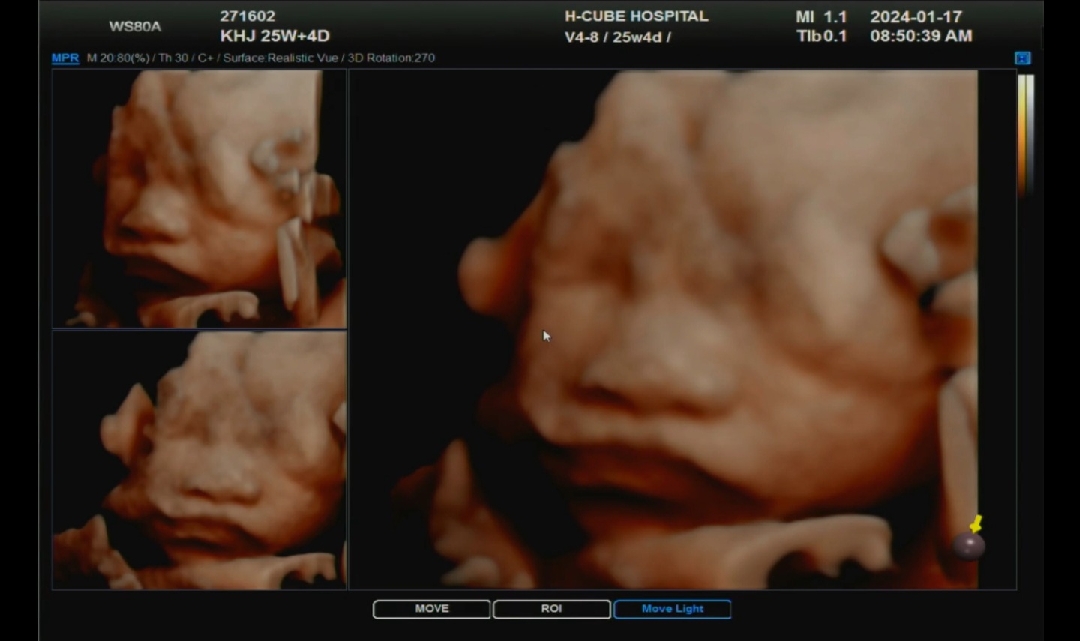

25주 4일차 협조 잘해주내요

임당검사랑 함께 임초보고 왔어요 25주 4차인데 협조 너무 잘해주더라구요 초음파 20분만에 다 보고 나왔오요!! 다만 고위험 산모이다 보니 호흡곤란이나 깨질듯한 두통, 다리사이 뭔가 흐르는 느낌 나면 바로 병원으로 와야한대요 ㅎㅎ 곧 900g 되가는중인데 제 눈엔 이목구비도 또렷하게 잘 보여줘서 너무 좋았어여 !!